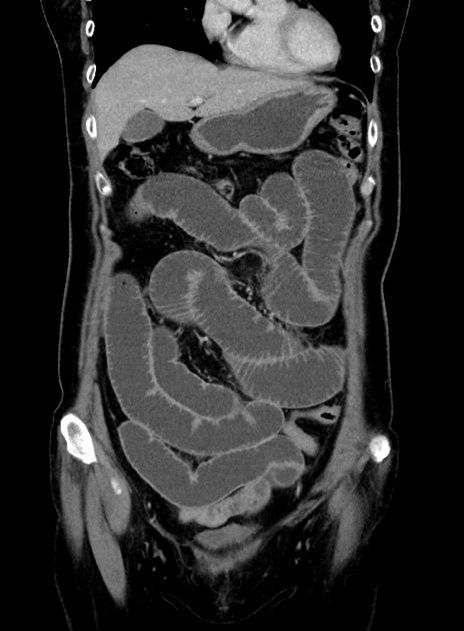

症例9(冠状断像)

【症例】 60歳代女性

【主訴】むかつき、みぞおちの痛み

【現病歴】3日前よりむかつきがあり、食事がとれない。

【既往歴】糖尿病

【身体所見】発熱なし、心窩部圧痛軽度あるも、腹膜刺激症状なし。

【データ】WBC 7400、CRP 1.92